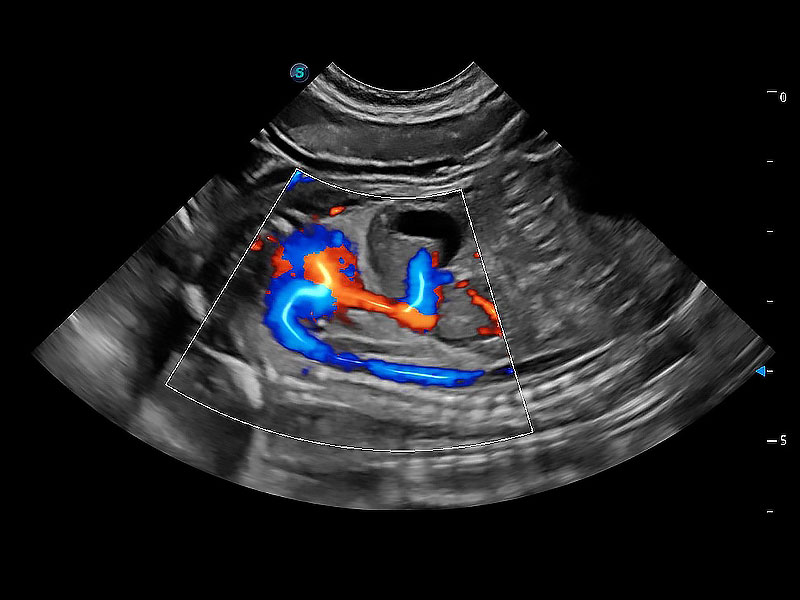

ProPet 80 配備了豐富的心臟探頭群、先進的成像技術(shù)和專業(yè)的心臟測量工具,可幫助動物醫(yī)生為不同體型和生理結(jié)構(gòu)的動物提供心臟和心肌功能的全面評估。